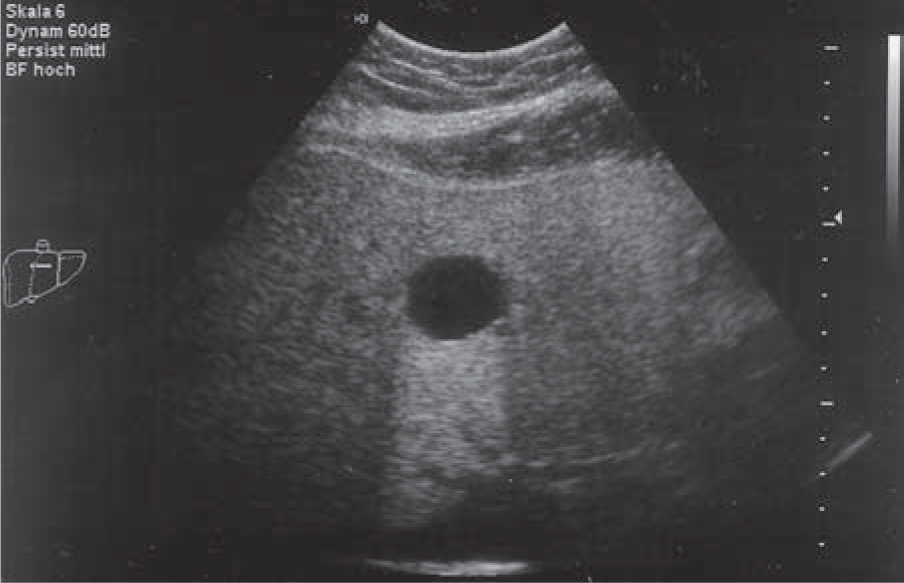

Polycystic liver disease ultrasound. Atlas of Ultrasound Erlangen - Germany Show menu Hide menu. Linear correlations between liver and spleen SWS spleen length and platelet counts were analyzed. Isolated polycystic liver disease IPLD is a rare genetic condition characterized by the presence of multiple liver cysts with no association with polycystic kidney disease.

However computerized tomography and magnetic resonance imaging are more sensitive for detecting kidney or liver cysts. Polycystic liver disease PLD is usually associated with polycystic kidney disease but may also occur as an isolated finding as a rarer genetically distinct disease. Department of Radiology University of Colorado Medical Center 4200 East Ninth Avenue Container C277 Denver Colorado 80262.

Polycystic liver disease PLD is a hereditary condition that may arise either in patients with autosomal dominant polycystic kidney disease ADPKD or in patients with a different genetic mutation that results solely in autosomal dom-inant polycystic liver disease. In either case the cyst burden will progress over time and in rare cases may affect liver function. A normal liver has a smooth uniform appearance.

Ultrasound Of Polycystic Liver Disease Ultrasound Guided Polycystic Liver Disease Patient Shares Experience With Her An Ultrasound Scan Of The Right Lobe Of The Liver In A 19 Cystic Liver Lesions An Ultrasound Perspective Geir Folvik Md Division Of Gastroenterology Department Of. The prevalence of pancreatic cysts in the 187 persons in whom the pancreas was well evaluated sonographically was 5. Imaging techniques including abdominal ultrasounds computerized. Polycystic liver disease is defined as a liver containing more than 15 unilocular cysts. A normal liver has a smooth uniform appearance. However computerized tomography and magnetic resonance imaging are more sensitive for detecting kidney or liver cysts. This video shows Cystic disease of the liver and kidneysPolycystic liver disease PLD or PCLD is a rare condition that causes cysts -- fluid-filled sacs --.